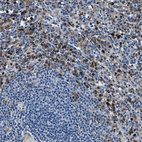

Immunohistochemistry analysis in human spleen and pancreas tissues using HPA021011 antibody. Corresponding FGL2 RNA-seq data are presented for the same tissues.